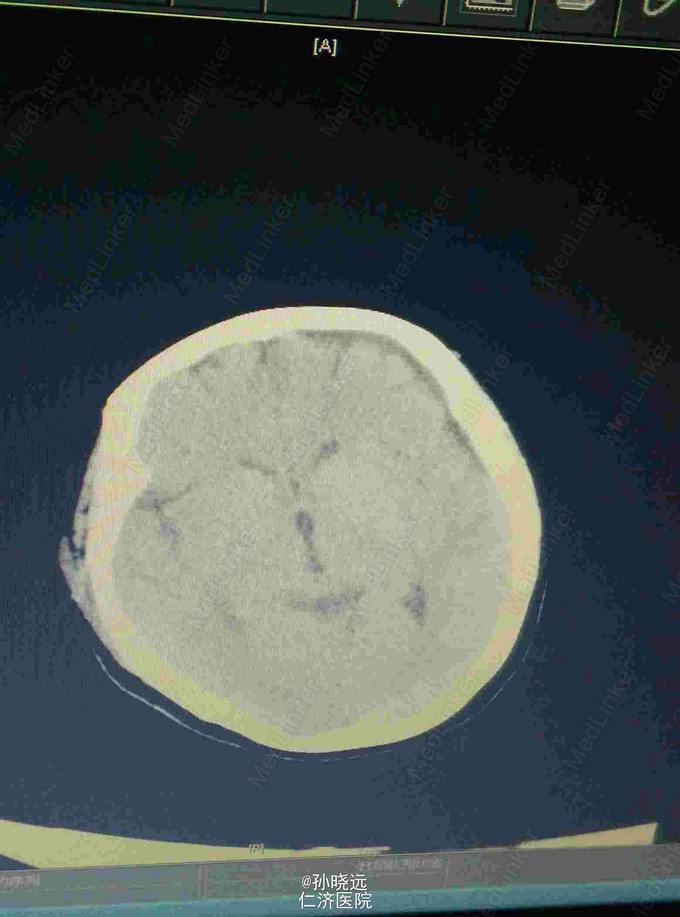

中年女性。主诉:头晕三天,发热伴神志不清1天。 患者于三天前出现持续性头晕,无恶心、呕吐,无视物旋转,来院就诊,查头颅MRI未见异常,予桂哌齐特、长春西汀、硫辛酸治疗,症状无好转。1天前出现高热,最高39.5℃,无咳嗽、气促,再次来院就诊,查血常规:WBC:5.85*10^9/L,N:71.8%,CRP正常,予退热,阿奇霉素等治疗,今日凌晨出现神志不清,无抽搐、恶心、呕吐,头颅CT示两侧颞底部不规则斑点样密度增高影并周围低密度灶,考虑脑炎合并灶性出血,予更昔洛韦、醒脑静、喜炎平、奥美拉唑、甘露醇治疗。后出现氧饱和度下降,予气管插管有创呼吸机辅助通气。 既往史:曾有高血压病史,未应用降压药。

查体:T:39.7℃,BP:180/120mmHg,神志不清,无法对答。双侧瞳孔等大等圆,直径0.15cm,对光反射迟钝,鼻唇沟对称。颈项强直。四肢肌张力正常。肌力检查不合作。双侧膝反射存在。双侧巴氏征阳性。克氏征、布氏征阳性。颈静脉无怒张,气管居中,两肺呼吸音粗,可及少量湿罗音。心率112bpm,未及杂音。腹部查体均正常。

诊断:脑炎。脑出血。 治疗:甲强龙抗炎,更昔洛韦,青霉素钠抗感染,降压,甘露醇、甘油果糖、白蛋白、拖拉塞米里降颅压,呼吸机辅助通气等对症治疗。

腰穿是: 脑脊液生化:葡萄糖:12.18mmol/L,CL:110.9mmol/L,蛋白:222.4mg/dl, 脑脊液常规:淡黄,微混。红细胞:1000*10^6/L,白细胞:1059*10^6/L,潘氏试验阳性(++++),嗜中性粒细胞12%,淋巴细胞:80%,单核细胞8%,凝块无,细菌未找到。 予加用血必净,加强抗感染等治疗。 患者目前仍昏迷,正进行高压氧仓治疗。这是最近一次复查的头颅CT。